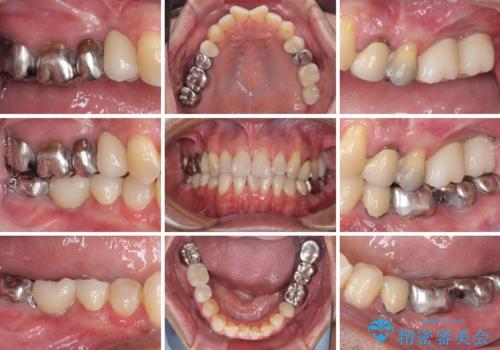

左上の奥歯は2本抜歯が必要であったため、治療期間中は右側に負担がかかり、頻繁に仮歯が壊れてしまいました。

左上に仮歯が装着されたからは咬み合わせが安定し、スムーズに治療を進めることができました。